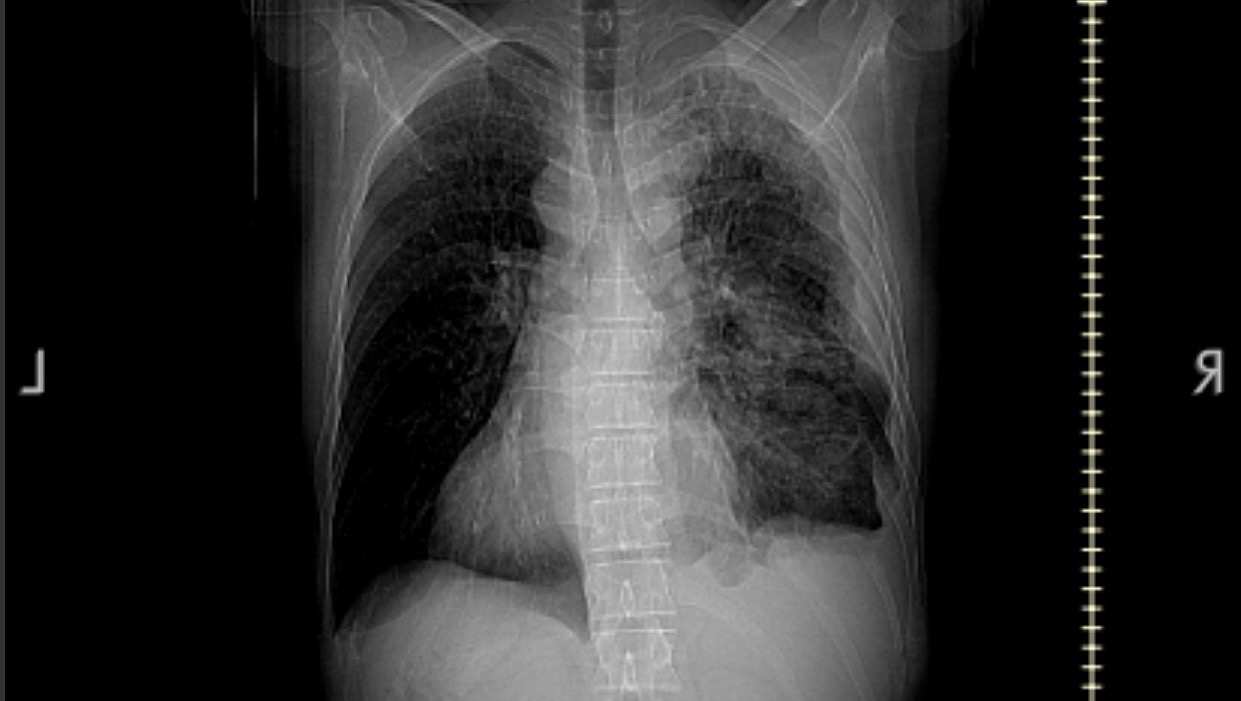

My name is Ryan Nestor. I’m 42 years old and recently I found out I have stage 4 lung cancer. Unfortunately it’s in the pleura surrounding my lung and it’s rare. The best I can hope for is treatment to make me comfortable, recovery would be a miracle. It’s taken like 80% of my functionality, so working or even basic activities are extremely difficult for me. I can’t do really anything I used to like to, anything physical is too much unless it’s very brief. I’m asking for help because I can’t work and I’ve applied for disability benefits, but they take time to be approved. Anything will help. Thank you.